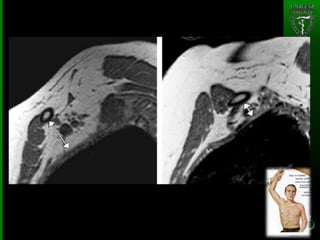

• #20 - Scalenus minimus muscle in a 35-year-old woman with neurologic TOS. Sagittal gross anatomic section(a)and sagittal T1-weighted MR image(b)show a scalenus minimus muscle (straight arrow), which passes between the C8 nerve root (arrowhead) and subclavian artery (curved arrow).